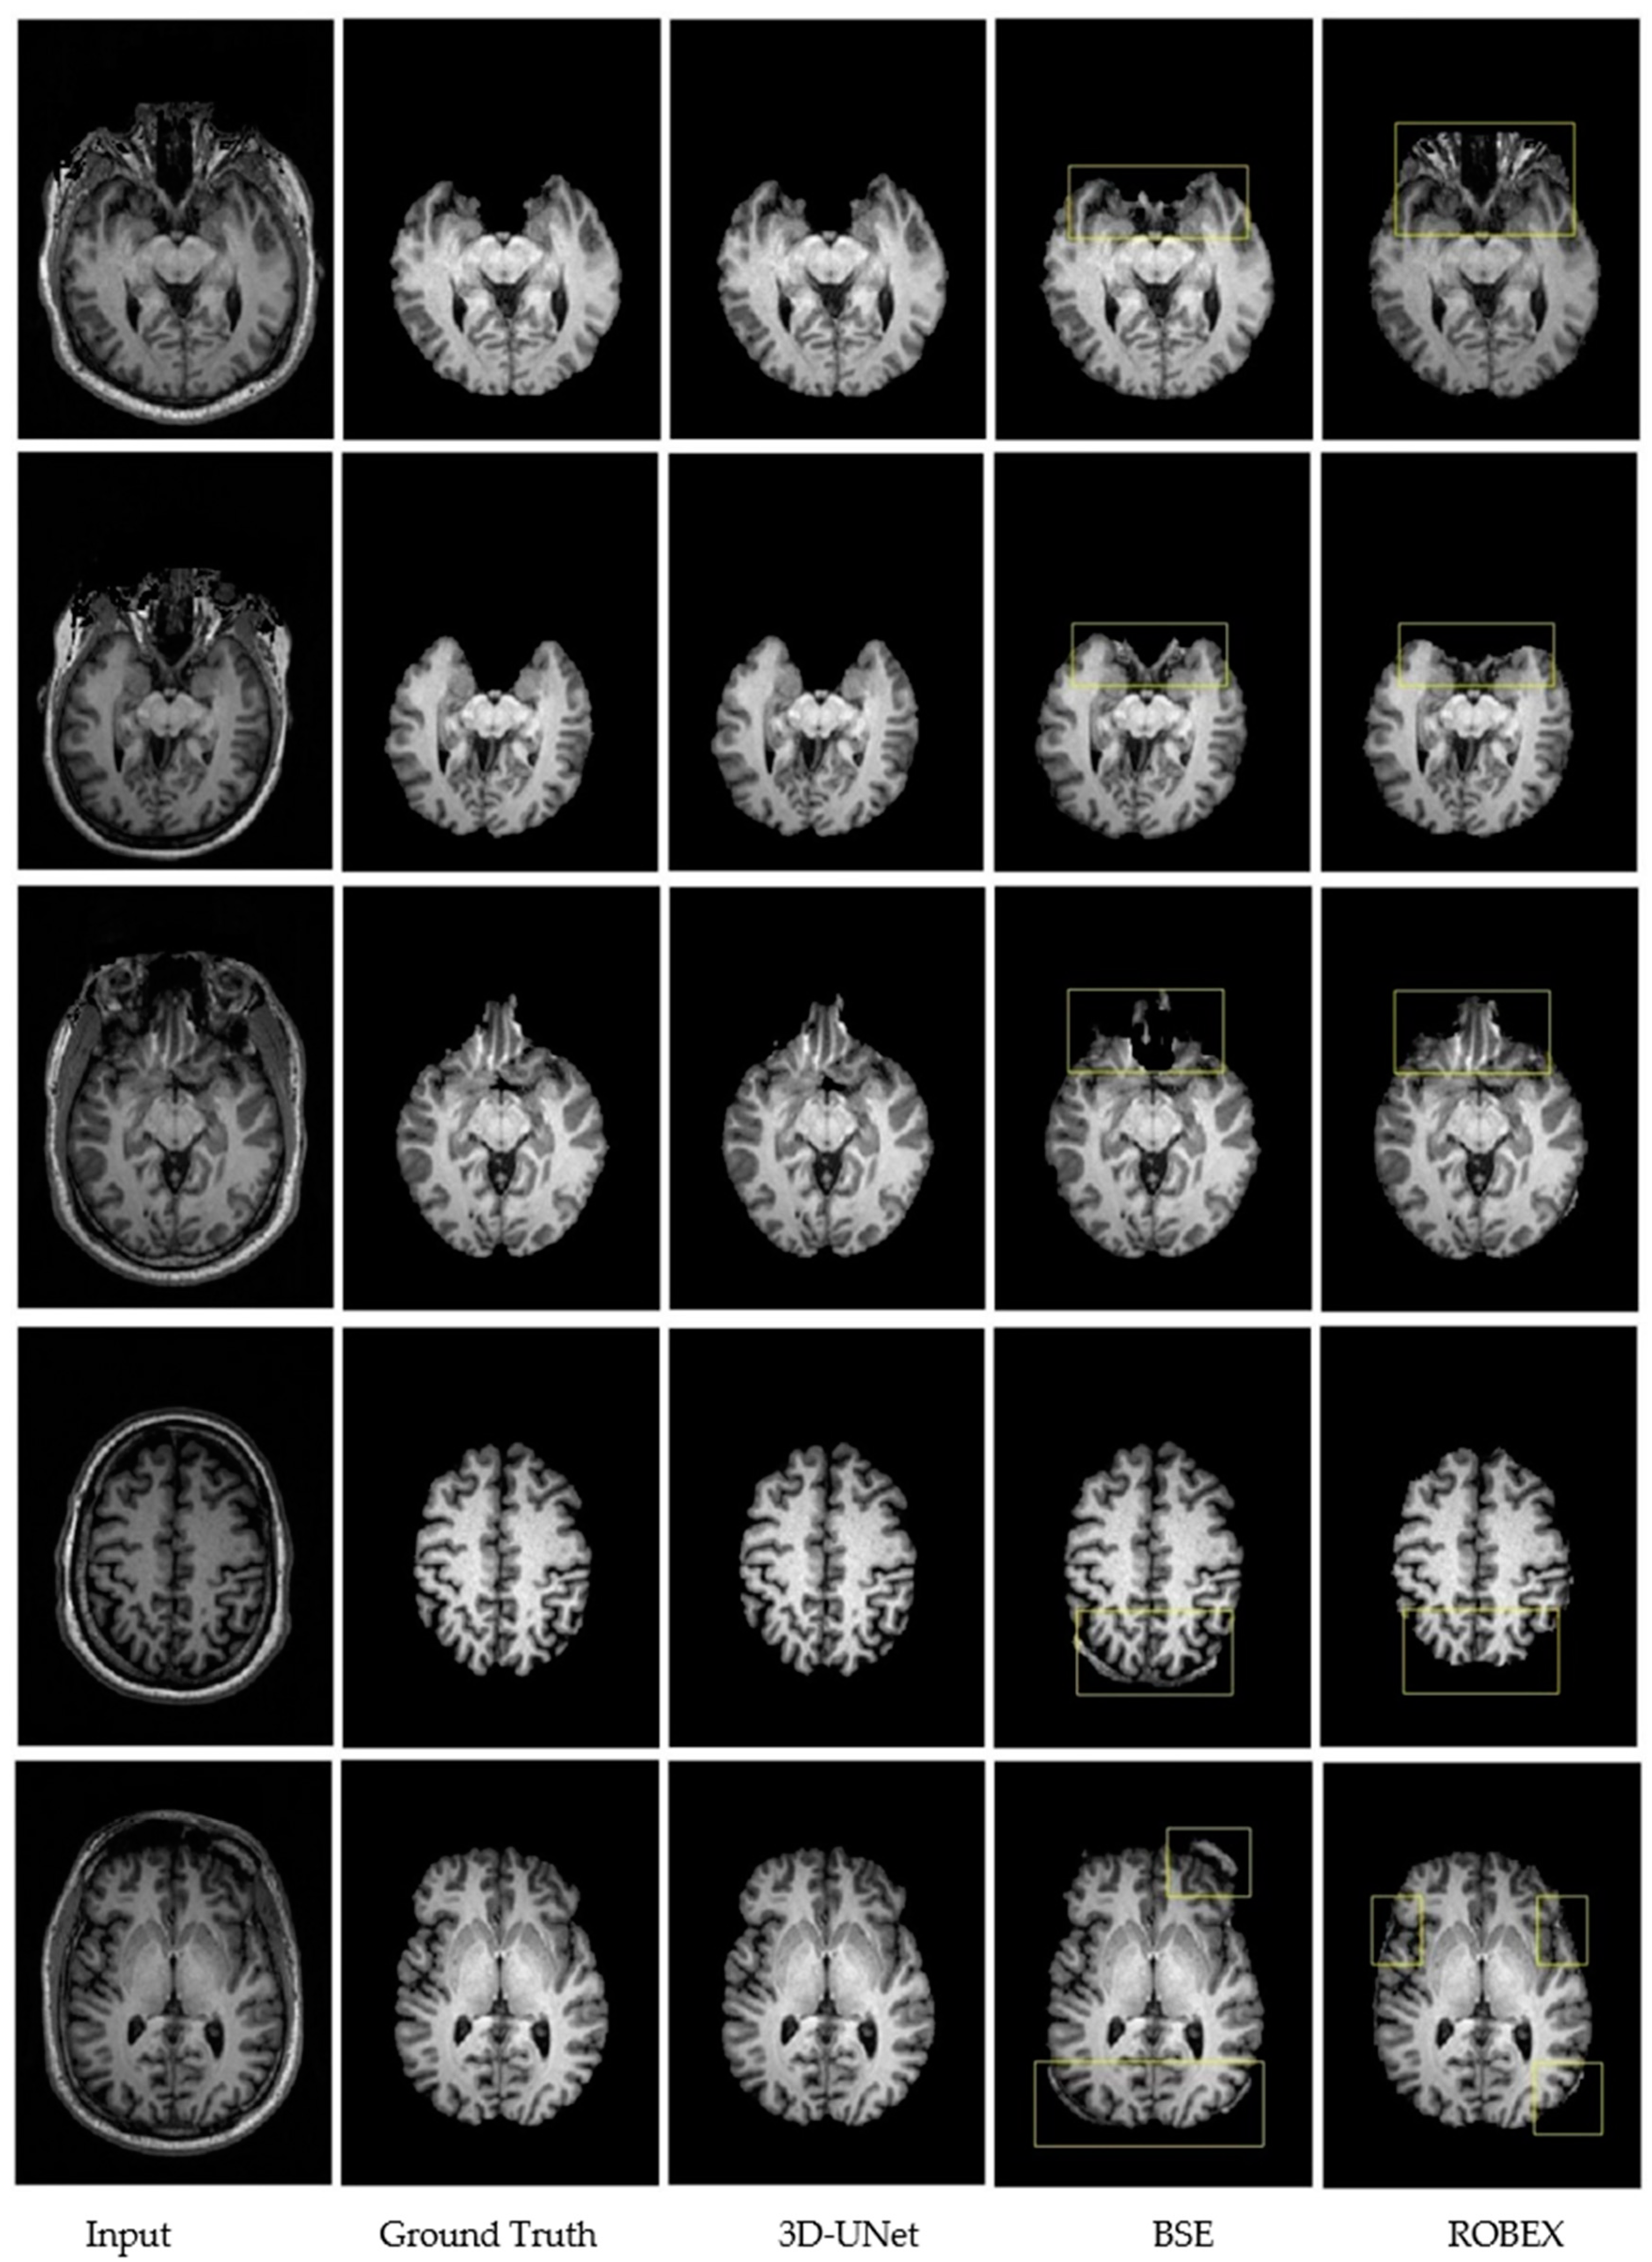

3.3. Qualitative Results.